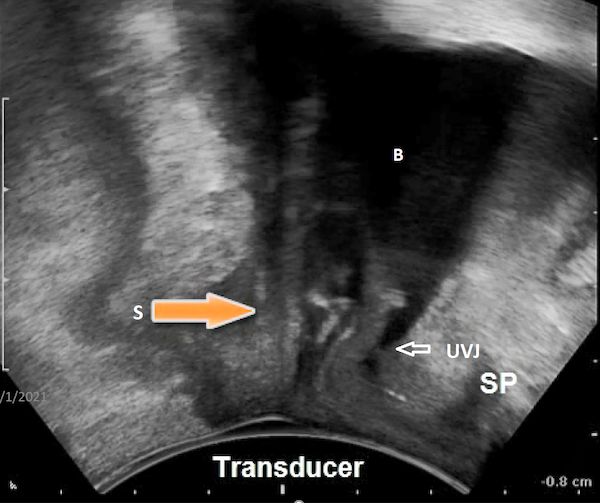

Figure 6

Transperineal ultrasound image in the midsagittal plane: transobturator sling is curved at rest and maximal Valsalva and located proximally. B: Bladder; U: Urethra; S: Sling; SP: symphysis pubis; T: transducer

The best outcomes following mid-urethral transobturator sling surgery as well as TVT sling surgery were found to be associated with concordance of urethral movement with the sling and mid-urethral location at maximal Valsalva followed by deformability of the sling on dynamic assessment (Hegde et al 2014). However, the three parameters often work together to compensate for the failure of an individual parameter to ensure successful outcome (Hegde et al 2014). A patient in whom the sling does not deform on Valsalva (i.e., does not curve into a C-shape from flat at rest along its width) may still have a successful outcome if the sling is in the correct location (mid-urethral) at rest and the urethra moves in a concordant manner with the sling (Hegde et al 2014).

When the urethral movement is discordant, i.e., the urethra moves independently of the sling on dynamic assessment, it indicates that the sling has not fixated itself to the suburethral connective tissue. It could also imply that the sling has been inserted too loosely such that even though the sling has scarred in following surgery, there is no tissue bridge between the suburethral tissue and the sling (Hegde et al 2017). Therefore, even if the sling is located mid-urethrally at rest, it cannot cause dynamic compression of the urethra on dynamic assessment as the urethra moves independent of the sling.